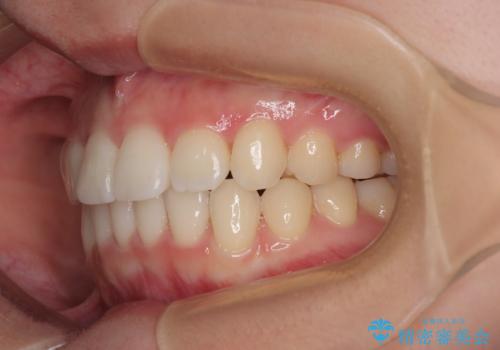

- 上下前歯のデコボコを気にして来院された患者様です。

ワイヤー矯正でもマウスピース矯正でも可能でしたが、短期間で、自身の手を煩わせることなく治療を行いたいとのことで、ワイヤー装置にて矯正治療を行うこととしました。

舌の突出癖により、出っ歯仕上がりとなる可能性がありましたが、舌のトレーニングを頑張っていただき、1年強で終えることができました。